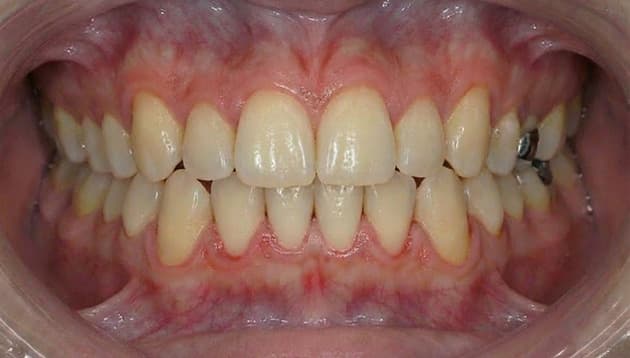

上顎部分矯正症例

- 症例について詳しく見る

-

症例名 上顎部分矯正/上の前歯のガタガタ 患者さまの主訴 小さい頃に矯正したが後戻りしてきた、上のガタガタ治したい 治療内容 上顎部分ワイヤー矯正 患者さまの年齢 36歳 患者さまの性別 男性 治療期間 5ヶ月 治療にかかった総額 33万円(税込) 治療する際に起こるメリット 治療により、見た目の改善、噛み合わせ・咀嚼機能の改善、清掃性向上(虫歯・歯周病リスク低下につながる場合)などが期待できます。

※効果には個人差があります。治療する際に起こるリスク・副作用 治療には、疼痛・違和感、虫歯/歯周病リスク、後戻り(矯正)、歯肉退縮などの可能性があります。